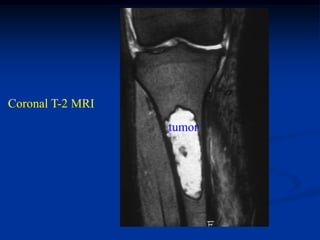

Case #555

55 year male

enchondroma

tibia

Coronal T-1 MRI

Coronal T-2 MRI

tumor